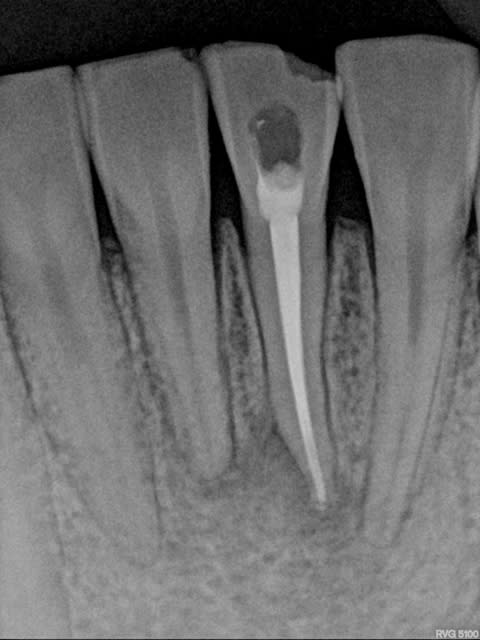

voila la radio

Radio da5wtg - Eugenol

La position entre incisive latérale et canine au maxillaire, la forme de "poire inversée" et la légère divergence des racines peuvent faire envisager un "kyste globulo-maxillaire", terme qui ne désigne plus un diagnostic mais seulement une localisation selon l'article ci-dessous :

http://www.sso.ch/doc/doc_download.cfm?uuid=9559FF39D9D9424C4C431470CC567372&&IRACER_AUTOLINK&&

L'article décrit le différentiel pour ce type de lésion. La nécrose n'est peut être venue que secondairement "a retro".